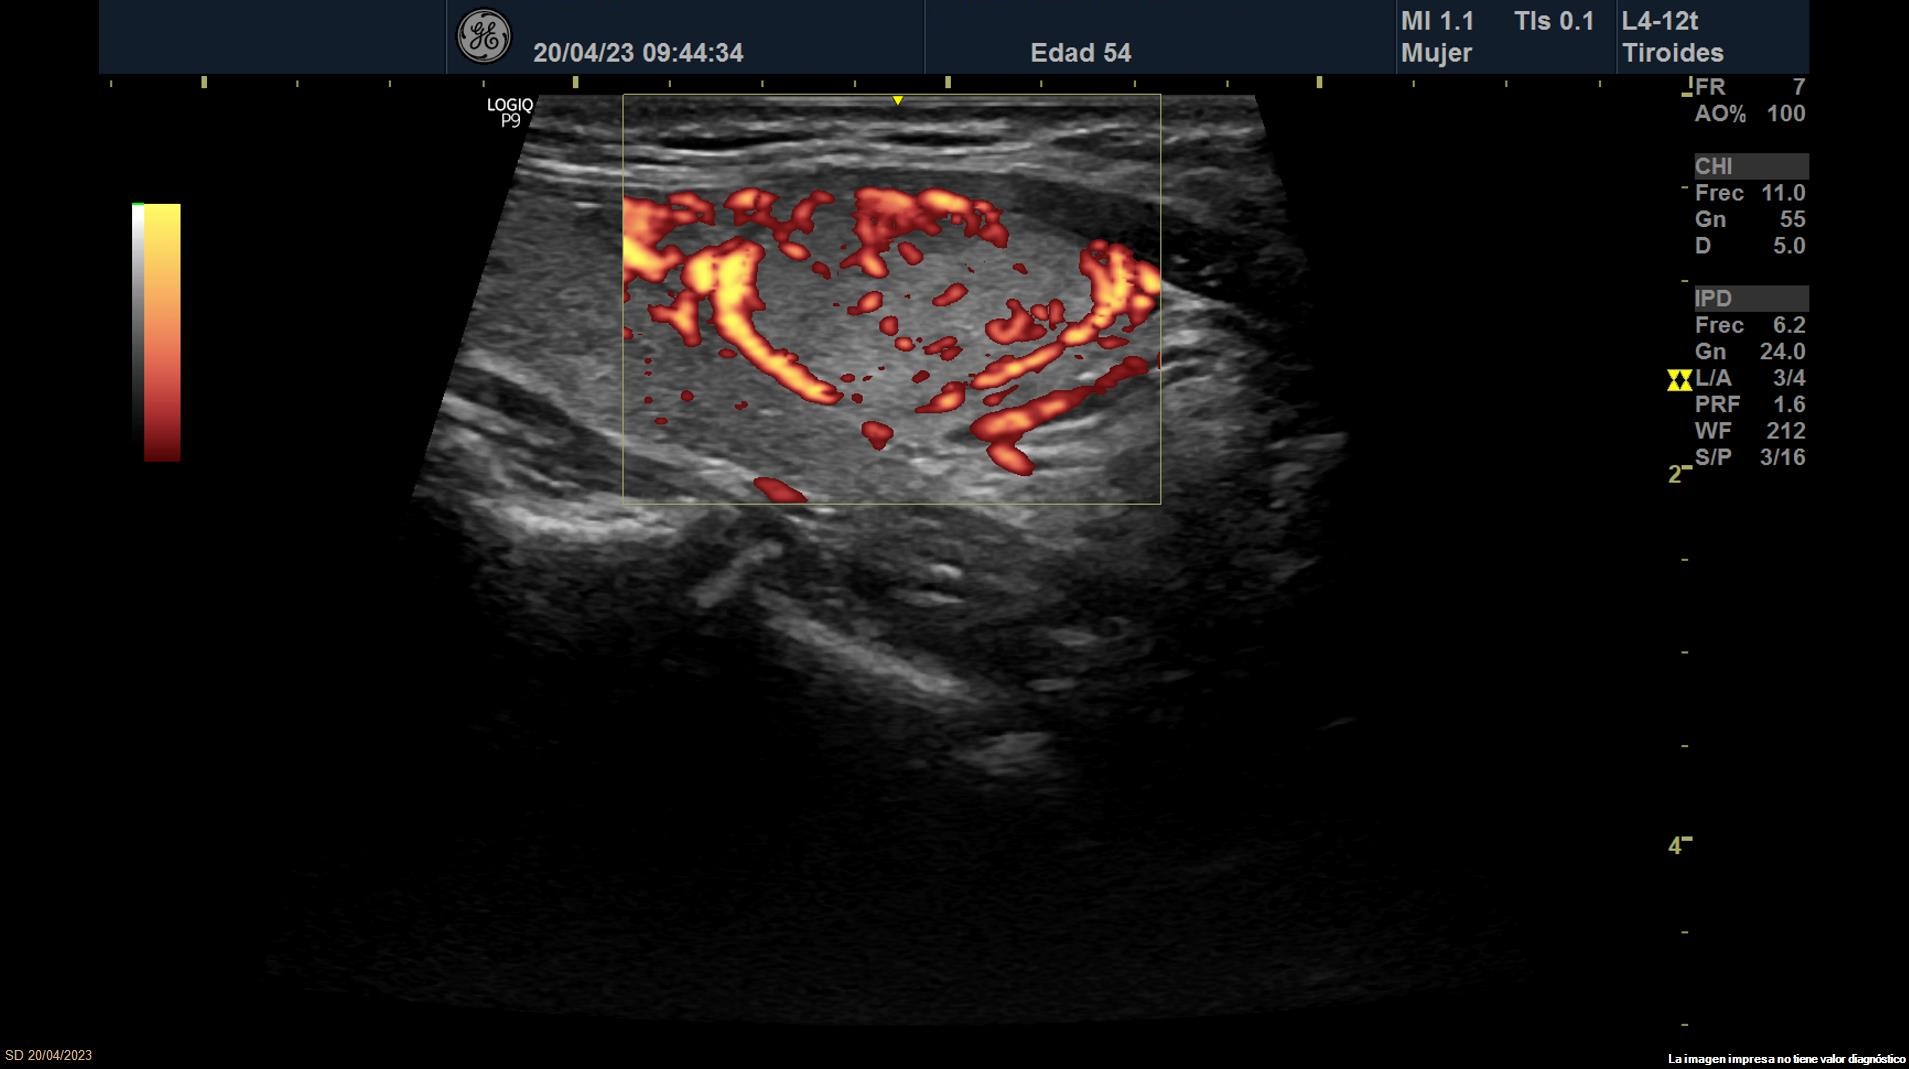

Se objetiva una adenopatía de 0,8 cm de aspecto benigno, ovalada y con bordes definidos. Además, se realiza ecografía tiroidea:

• Lóbulo tiroideo izquierdo: tamaño normal. En la mitad inferior se objetiva un nódulo de 11 x 14 x 20 mm (Vol 1,52 ml), bien definido, sólido e iso/hiperecoico, con halo fino hipoecoico, sin calcio y con vascularización de predominio periférico (ATA: baja sospecha).